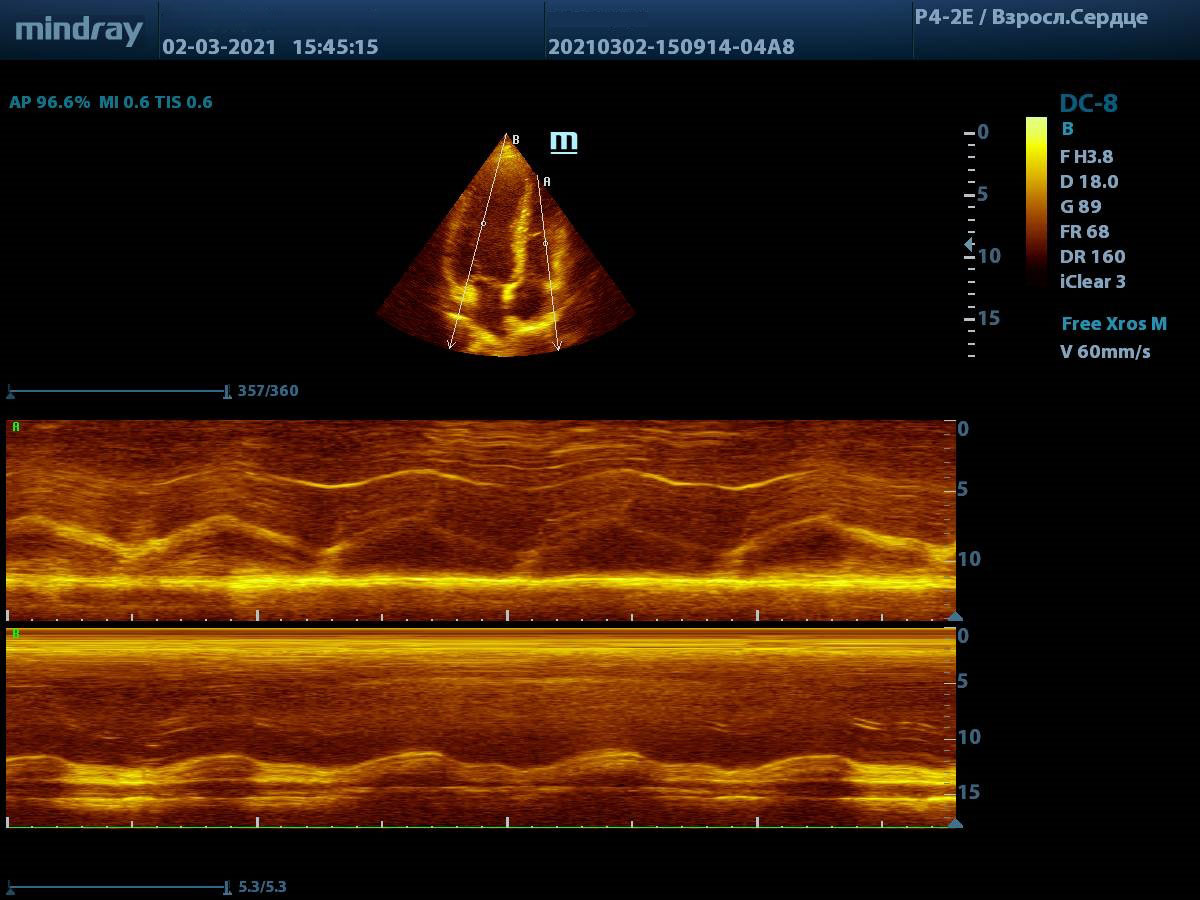

Продвинутые операторы диагностической техники также владеют методами оценки функции желудочков в режиме Free Xros – свободном М-режиме. Такие параметры как TAPSE позволяют быстро и удобно оценить сократительную функцию правого желудочка, нормальное значение движения амплитуды кольца трикуспидального клапана 17 миллиметров или более.

Левый желудочек не остается в стороне, для него есть показатель MAPSE – измеряется в М-режиме и пересчитывается во фракцию выброса левого желудочка. Показатель более 10 мм считают нормой. Для расчета фракции необходимо подставить значение в формулу EF = 4.8 × MAPSE (mm) + 5.8. Такой способ оценки применяется только у взрослых. Использование нескольких срезов одновременно с функцией Free Xross позволит оценить сразу оба желудочка, что сильно экономит время и силы к концу трудового дня.